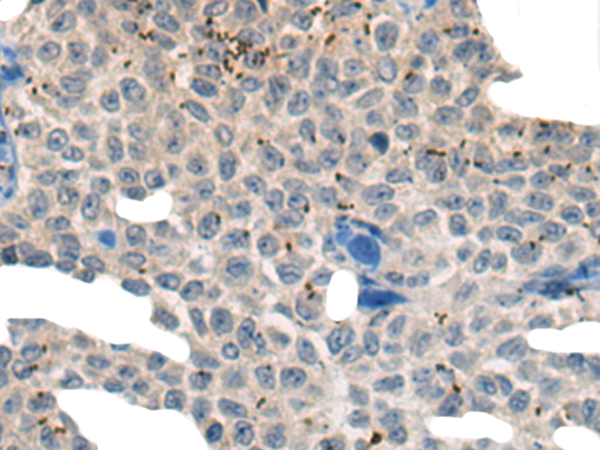

分类: 科研抗体货号: P13166别名: TIM3; CD366; KIM-3; TIMD3; Tim-3; TIMD-3; HAVcr-2应用: IHC反应种属: Human